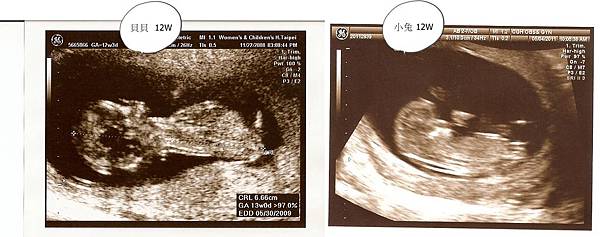

上周產檢時照超音波,看到小兔可愛的樣子囉

小手小腳不停揮舞,感覺也是個活潑的寶寶

不過比起貝貝才12W產檢時,就不停整個人在羊水裡開心的上下跳動,醫生還要等他不那麼high時才照的到超音波,小兔算是比較文靜的了

來個比較圖

最明顯的就是 -- 這麼小就看出兩個都有"扣桃"啦!只能說小鳥先生的遺傳基因實在太強了